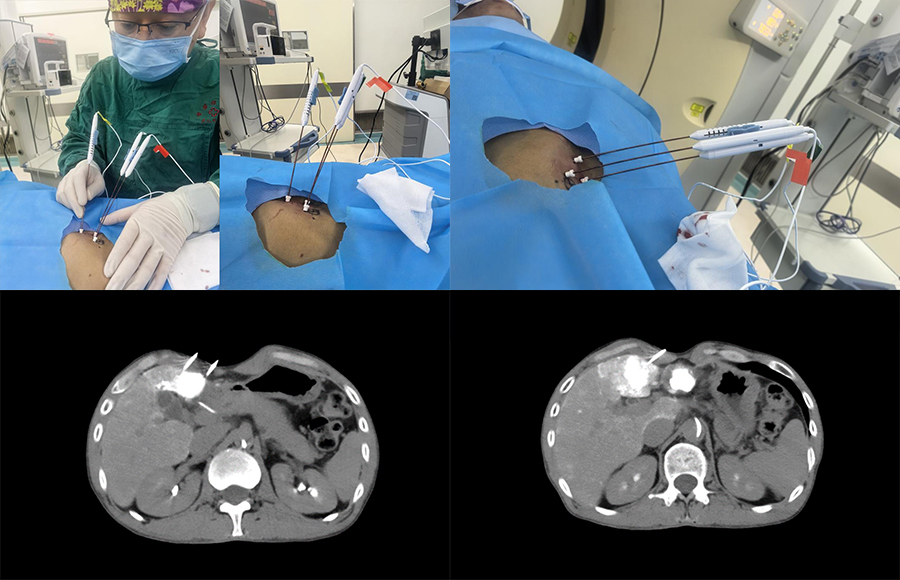

▲ 患者一手术过程

▲ 患者二手术过程